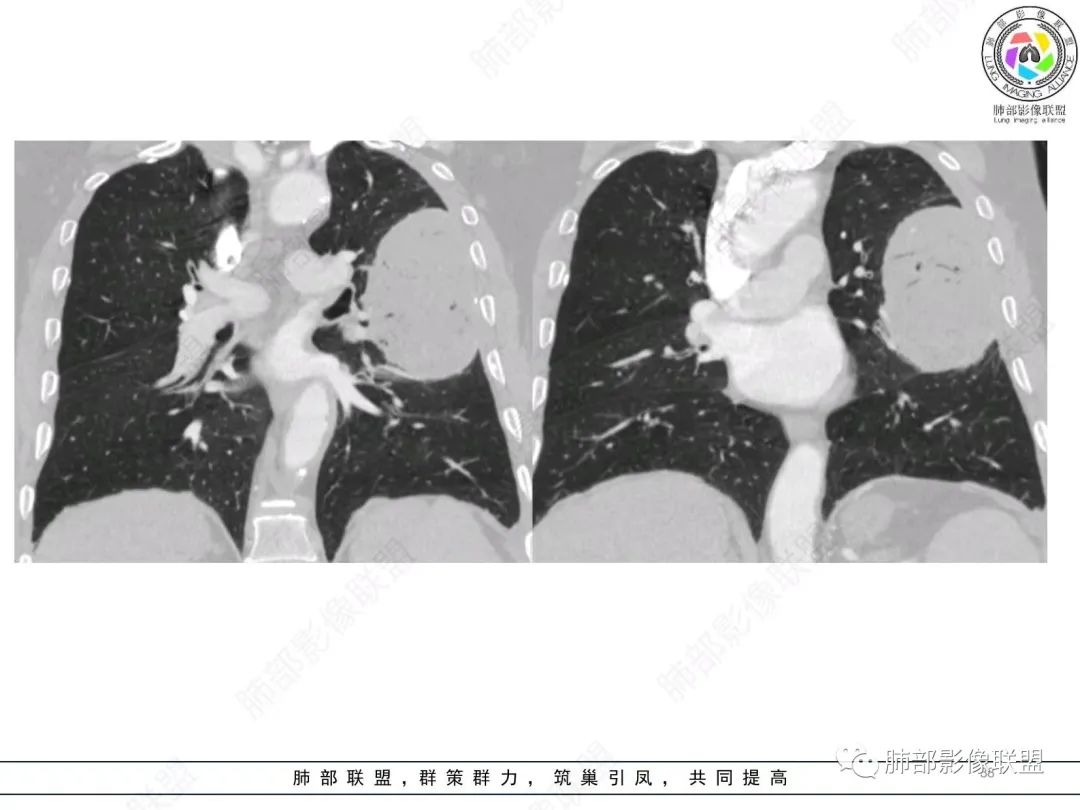

我再建一下血管。支气管进入,但是近端推移,堵塞

大肿块,边缘光滑,深分叶

近端支气管堵塞、推移为主

部分类似于脐凹征

内部支气管扩张

肺动脉推移为主,边缘部分进入

淋巴瘤符合吗?

大肿块、表面光滑但深分叶,肺门侧支气管堵塞

回头看,内部支气管近端其实不连续,伴随肺动脉不存在

这两点就不符合

还有如果从支气管的特点考虑黏膜相关性淋巴瘤,其整体应该是边缘不清楚为主,肺炎样为主。

1)部位:周围型或中央型软组织肿块,以周围型为多见,且肿瘤多位于肺上叶。如本例:该肿瘤位于左肺上叶。

3)肿块边界和边缘:多较清楚,呈圆形、类圆形,且由于肿块生长速度不均匀,可见分叶,毛刺少见。有报道肿块周围毛玻璃影是多形性癌特征表现。

5)肿瘤强化方式:肺部恶性肿瘤强化程度与其血供丰富程度相关,血供丰富多强化明显,反之则较差。由于PSC 周边实性部分富血供及内部黏液变性、坏死,增强后肿块多数呈轻-中度边缘环形强化或不均匀小斑片状强化。国外学者对照病理发现肿瘤细胞或胶原组织增强扫描时强化,无强化的低密度区代表了黏液样变性区和出血坏死区。